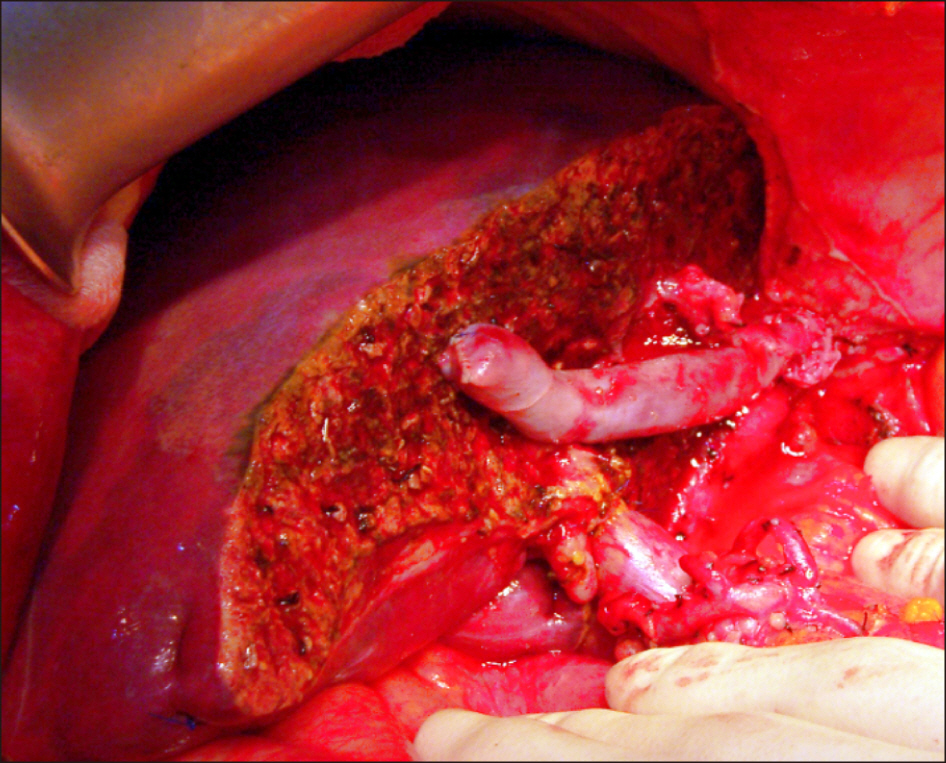

- The feasibility of liver transplantation (LT) for colorectal liver metastasis (CRLM) is still under investigation with only a limited number of LT cases in literature. CRLM is the most common type of liver metastasis, but it was considered as a contraindication to LT for a long time because of poor outcomes. We presented a case of living donor liver transplantation (LDLT) performed in a patient with liver cirrhosis and CRLM. The patient was a 49-year-old female with sigmoid colon cancer and synchronous multiple CRLM. She underwent anterior resection for sigmoid colon cancer and 7 sessions of chemotherapy for CRLM. She suffered from esophageal varix bleeding due to chemotherapy-associated liver cirrhosis. Because of liver cirrhosis and multiple CRLM, the patient underwent LDLT operation using a modified right lobe graft. Serum chorioembryonic antigen level was 220 ng/mL at LT. Explant liver pathology showed multiple metastatic adenocarcinomas of colonic origin, up to 4.7 cm in the greatest dimension. The patient did not receive any specific anti-tumor treatment after LT. She is doing well without any tumor recurrence to date for more than 13 years after the LDLT operation. The experience on our case and literature review suggest that CRLM is not always contraindicated for LT because some selected patients showed improved long-term survival outcomes.